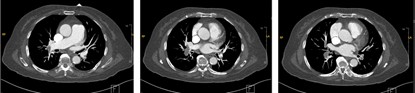

旋即病人血壓收縮壓掉到90+ mmHg,緊急電腦斷層攝影呈現:

哇!趕快給予肝素(heparin)、訂加護病房床位,並且告訴心血管科醫師堵塞的是肺動脈、不是冠動脈。亡羊補牢再次仔細評估病人,心電圖固然有傳說中的S1Q3T3,但是沒有肺梗塞最常見的心軸右偏(right axis deviation)與心率過速(tachycardia)……PoCUS唯有將左側乳房往上推才看得到4-chamber view。原來心室中膈動得較差是被脹大的右心室壓迫所致,仔細尋找也可以看到McConnell's sign